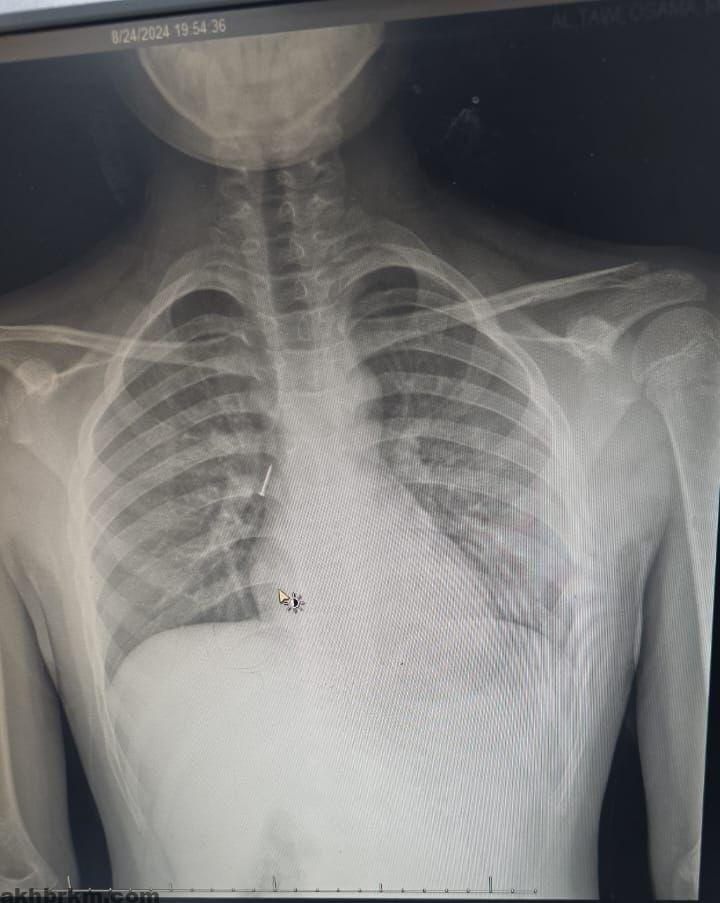

تمكن فريق طبي من قسم جراحة الأنف والأذن والحنجرة في مستشفى الملك خالد التابع لتجمع تبوك الصحي بمنطقة تبوك من انقاذ حياة طفل في العاشرة من عمره ابتلع مسماراً معدنياً مما تسبب له في ضيق في التنفس في الجهة اليمنى من الرئة وتضييق في الصدر.

وقال الفريق الطبي المعالج بأن الطفل وصل للطوارئ وكان يعاني من آلام شديدة في الحلق وضيق في التنفس وتم وضعه على الأكسجين بعد أن تم قياس العلامات الحيوية له , وبعد تقييم الحالة من قبل أخصائي الطوارئ وأخصائي الأطفال وأخصائي الأنف والأذن والحنجرة تقرر نقل الطفل إلى العناية المركزة للأطفال كما تم عمل أشعة مقطعية دقيقة على الشعب الهوائية حددت مكان المسمار المعدني بدقة.

وأكد الفريق الطبي المعالج بأنه تقرر على الفور إجراء عملية عاجلة لاستخراج المسمار المعدني بمنظار الشعب الهوائية تحت تخدير كامل للطفل من قبل فريق جراحة الأنف والأذن والحنجرة والتي تكللت ولله الحمد بالنجاح ولقد استغرق إجراء العملية ساعة كاملة, بعدها خرج الطفل من المستشفى وهو يتمتع بصحة جيدة ,مع المتابعة في عيادة الأنف والأذن والحنجرة.